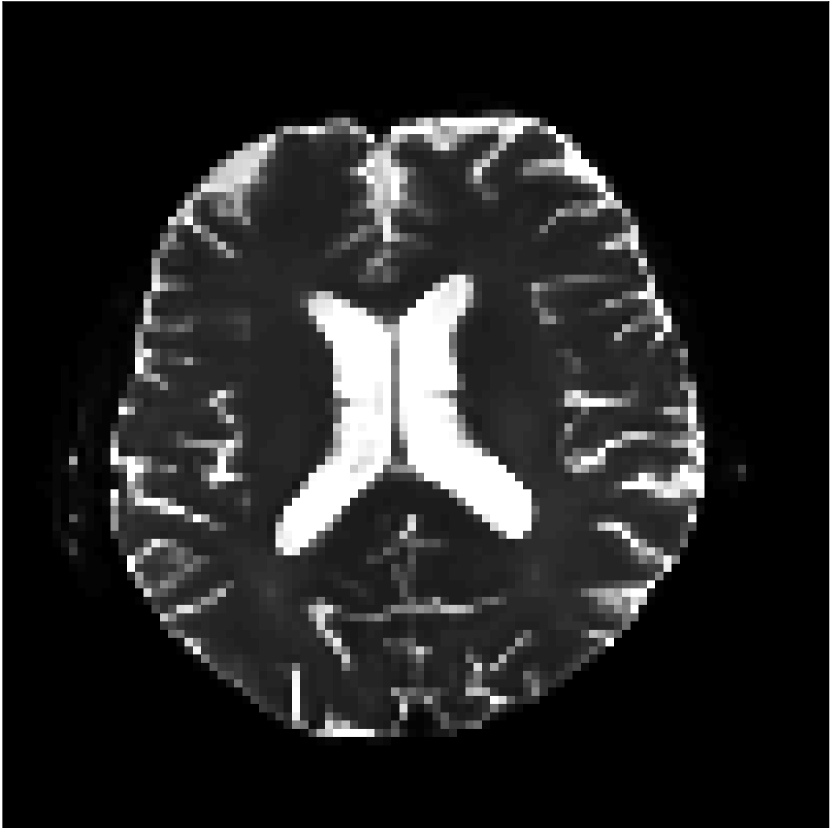

Figure 8 shows examples of non-diffusion-weighted images before and after processing. The raw images (Raw) served as the input for the magnitude deep learning (MCNN) and complex deep learning (CCNN) methods.

Raw

MCNN,

MCNN Resid.,

CCNN,

CCNN Resid.,

No PF

5/8 PF

Both methods remove artifacts, but the MCNN method allows residual rippling artifacts to pass through in the presence of partial Fourier. These rippling artifacts are not present in the CCNN method.